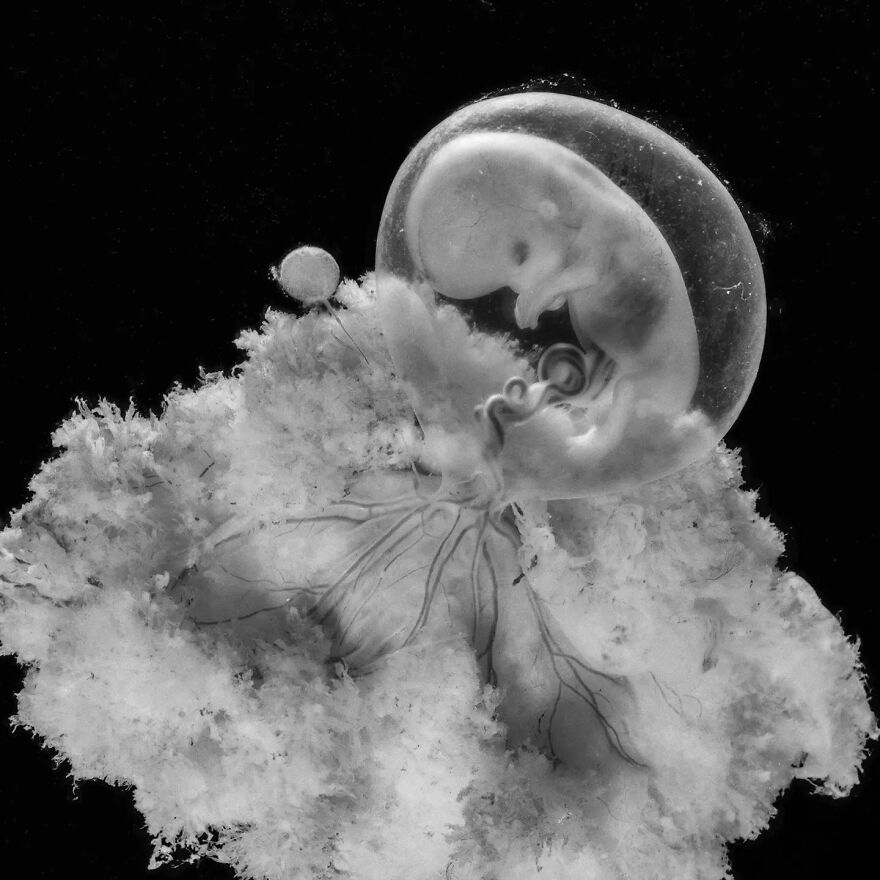

Снимки Леннарта Нильсона: развитие ребенка в утробе

Раздел: Мудрость в фокусе